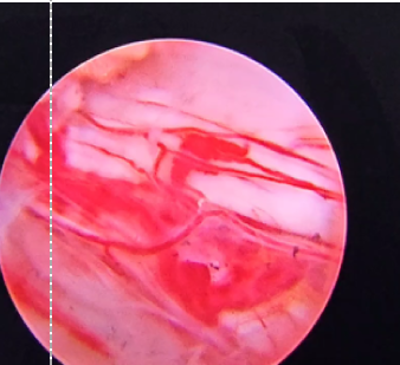

Dr. Khanna is also the recipient of the prestigious AO Spine International Fellowship from the globally renowned Schön Klinik, Munich, Germany, where he received training in advanced Endoscopic and Minimally Invasive Spine Surgery (MIS Spine Surgery).

Our team treats patients who need repair of spinal deformities due to scoliosis, kyphosis, spondylolisthesis, infection, tumors, and trauma — following international standards of care.